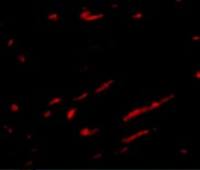

CD33

CD33 antibody [WM53]

WB, IHC-Fr, FACS, IP